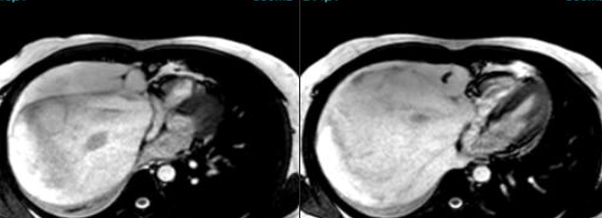

Tumors

The Heart Under Siege !